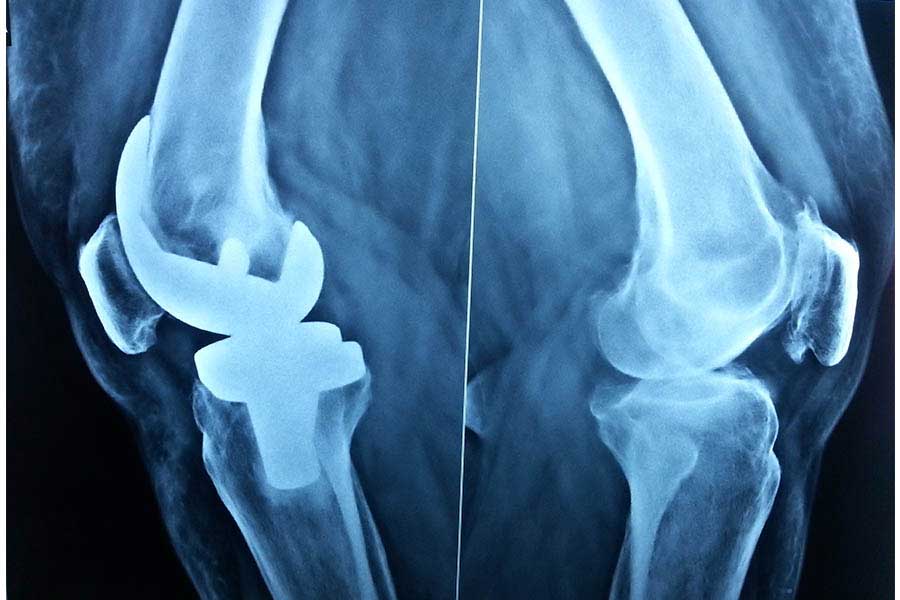

Total Knee Replacement

Case 1